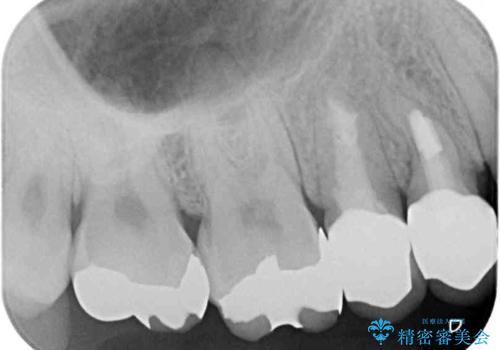

- 上の奥歯に装着されていた銀歯が外れてしまったとのことで来院された患者様です。

強い咬合力により銀歯と歯の間に隙間ができ、その隙間から虫歯となって外れてしまったと想像されました。

銀歯では歯と充填物の固さに違いがあり、再度外れてしまうリスクが高いため、固さが歯と近いゴールドインレー(PGAインレー)にて修復することとしました。